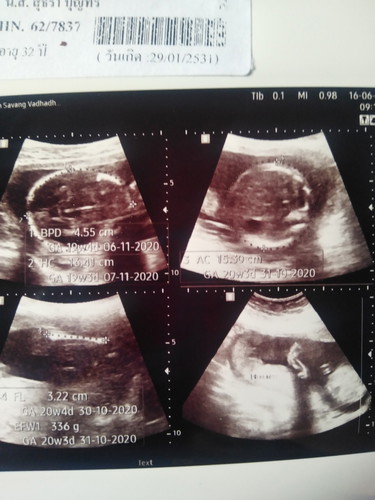

ทารก

อยากทราบว่าผู้หญิงหรือผู้ชายค่ะตอนซาวหมอไม่ได้บอกอะไรเลยค่ะ

จากภาพดูไม่ออกเลยค่ะ เวลาซาวสงสัยอะไรถามหมอเลยค่ะ ในนี้ไม่มีใครเก่งกว่าหมอ

ดูไม่ออกเหมือนกันจ้า